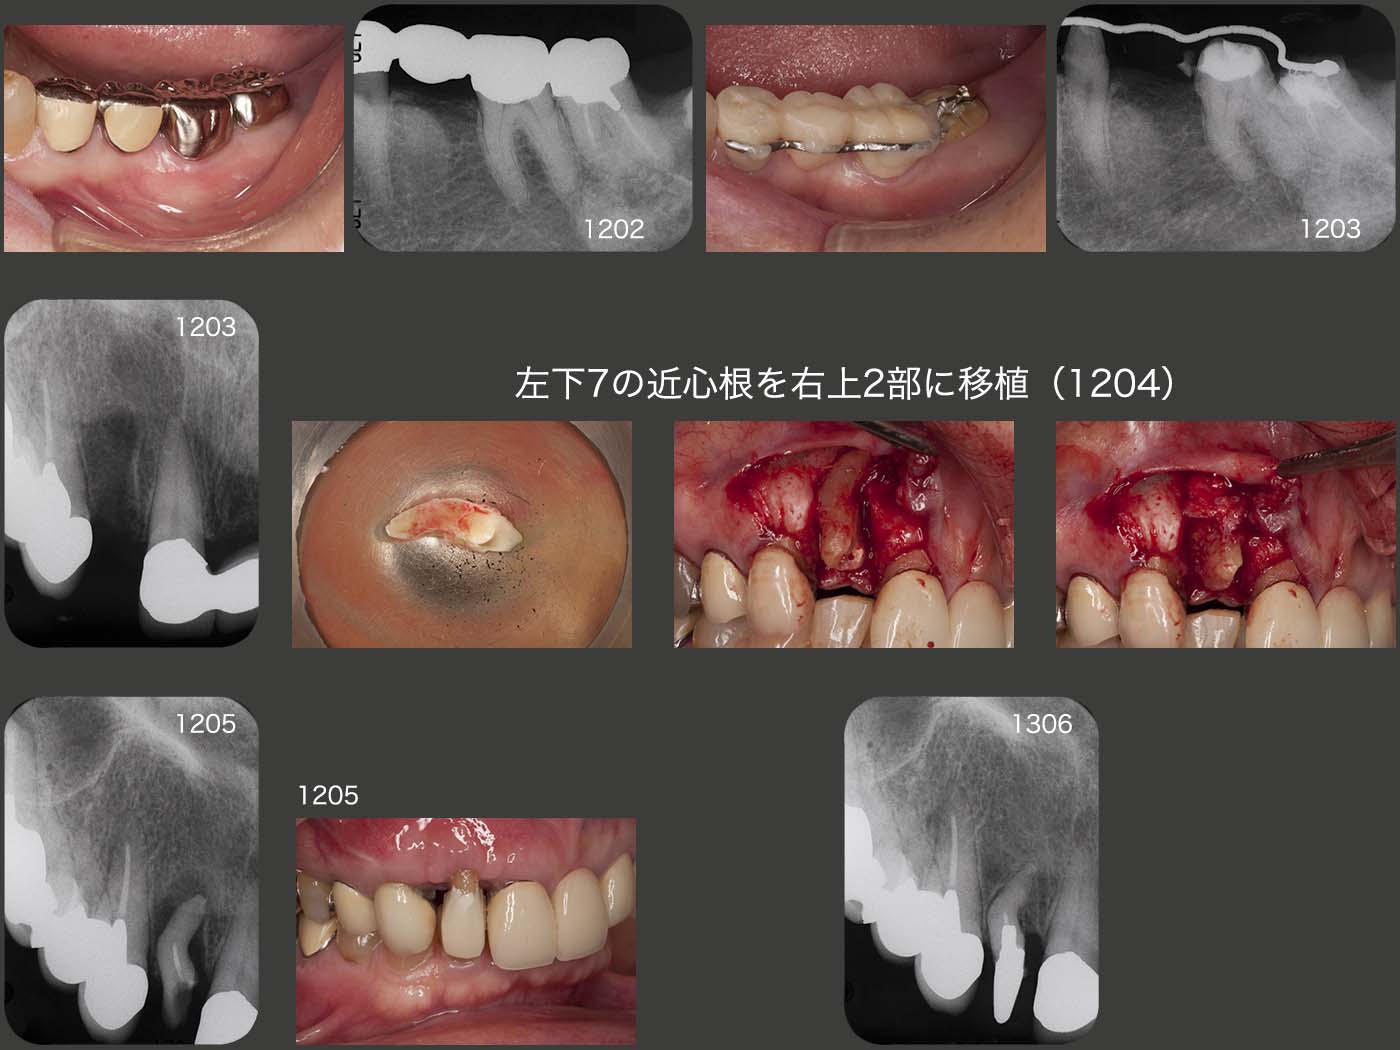

同部の補綴処置については,インプラントあるいはもう一度ブリッジを作り直す設計が考えられる.後者の場合,当院で装着した①1②のメタルボンド・ブリッジを作り直さなければならず,被害が大きい.また将来,無髄歯である右上3あるいは左上2に歯根破折が生じる可能性もある.ここで移植できるドナー歯がないかよく観察すると,左下7の遠心に10mmの歯周ポケットが存在した.そこで,この歯の近心根をドナー歯として利用する治療計画を立てた.

まず,左下7に挺出力を加え,抜去しやすいように細工した.この歯の動揺を確認後,2012年4月に左下7の近心根を右上2部に移植した.なお,遠心根は廃棄した.右上2部の抜歯窩の唇側には歯槽骨が全くなかったため,周囲の歯槽骨をメスで削ぎ落とし,これをドナー歯の唇側に被せることにより,同部の血餅の確保を期待した.なお,最近はフラップを開けず,直接抜歯窩にドナー歯を埋め込む術式を行っているが,どちらが良いのかはまだ判断できていない.また,歯根が湾曲しており根管治療が困難と予想されたため,根尖をスーパーボンドにて封鎖した.術後1ヵ月,移植された右上2の歯周ポケットは3mm以下であったが,歯頸部の歯肉が下がってしまったため,自然挺出が生じるように歯冠形態を調節した.

つぎに,埋伏している左下8を何とか左下7部の位置に歯科矯正で移動できないかチャレンジした.歯科矯正に拘ったのは歯髄を保存したいがためである.2012年5月,フラップを開け,歯冠周囲の歯槽骨を除去し,歯冠にフックを付与し,クローズドコイルを用いて引っ張り出そうと試みた.しかし,約1年間たっても変化がみられず,歯科矯正を断念せざるを得なかった.

13年6月,歯の移植による移動に切り替えることにした.矯正力を加えても動かなかったことから,癒着の可能性も否定できなかったが,意外に簡単に抜去することができた.左下7部にソケットを形成したのち,植立・固定した.歯科矯正が失敗したのは,歯冠周囲の歯槽骨の削去が不足していたのではないかと反省している.